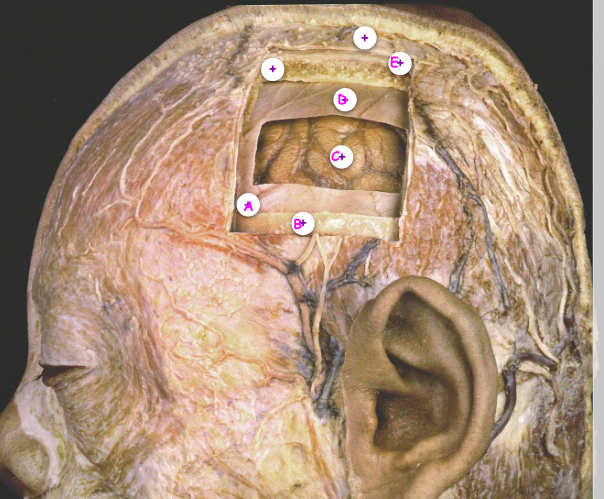

7

Q

Which of the following is the periosteum

A

B

C

D

E

8

Which of the following is the middle meningeal vessel

9

Which of the following is the arachnoid mater